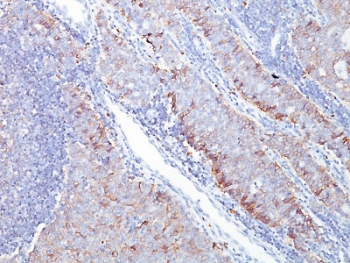

IHC staining of FFPE human ovarian carcinoma tissue with SLC2A1 antibody (clone GLUT1/7308). Inset: PBS used in place of primary Ab (secondary Ab negative control). HIER: boil tissue sections in pH9 10 mM Tris with 1 mM EDTA for 20 min and allow to cool before testing.